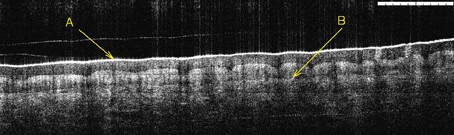

OCT is a technique for obtaining sub-surface images of translucent or opaque materials at a resolution equivalent to a low-power microscope. It is attracting a great deal of interest in the medical community, because of its potential to provide images of tissue morphology at a much higher resolution than is possible with imaging modalities such as MRI, or ultrasound. For example, the basal membrane in epithelial tissue can be seen in OCT images (Figure 1). Disruption of this basal membrane is an indicator of malignant cancer. Currently, medics have no alternative to the often-lengthy biopsy process - i.e. surgically removing the tissue and sending it to a histopathology laboratory for analysis. It is not surprising therefore that they are interested in the potential of OCT imaging to provide informative images, in real time.

| Figure 1: OCT image of skin tissue of palm of the author. The horizontal bar is 1mm. Note the stratus corneum (A) and basal membrane (B) |